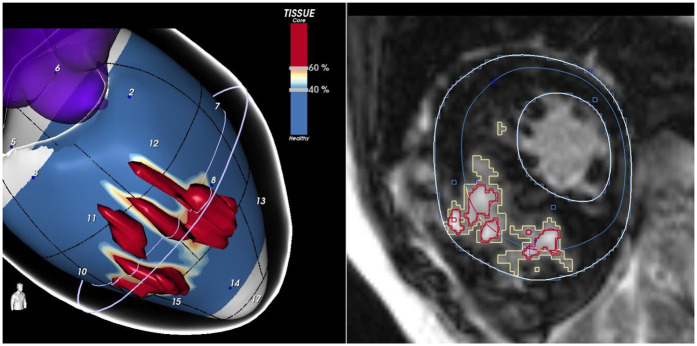

心肌瘢痕形成是肥厚性心肌病(HCM)的标志,也是不良后果的主要驱动因素,包括心源性猝死和心力衰竭进展。HCM的纤维化底物是复杂的,包括置换性和间质性纤维化,常伴有心肌紊乱。先进的心血管成像技术可以实现详细的疤痕特征,这对风险分层和个性化管理至关重要。心血管磁共振(CMR)是评估非侵入性纤维化的金标准。晚期钆增强、T1和T2弛豫特性心肌成像以及弥散张量成像等技术为了解疤痕负荷和结构提供了补充。心脏计算机断层扫描(CT)是一种新兴的模式,越来越多的临床意义。延迟碘增强和ct衍生的细胞外体积成像为疤痕评估提供了一种有价值的替代方法,特别是当CMR禁忌时。这篇综述强调了多模态成像在HCM心肌瘢痕评估中的作用,重点是CMR和CT,并探讨了它们的临床意义。

Myocardial scarring is a hallmark of hypertrophic cardiomyopathy (HCM) and a major driver of adverse outcomes, including sudden cardiac death and heart failure progression. The fibrotic substrate in HCM is complex, encompassing both replacement and interstitial fibrosis, often accompanied by myocardial disarray. Advanced cardiovascular imaging enables detailed scar characterization, which is crucial for risk stratification and personalized management. Cardiovascular magnetic resonance (CMR) is the gold standard for non-invasive fibrosis assessment. Techniques such as late gadolinium enhancement, myocardial mapping of T1 and T2 relaxation properties, and diffusion tensor imaging provide complementary insights into scar burden and architecture. Cardiac computed tomography (CT) is an emerging modality with increasing clinical relevance. Delayed iodine enhancement and CT-derived extracellular volume mapping offer a valuable alternative for scar assessment, particularly when CMR is contraindicated. This review highlights the role of multimodality imaging in assessing myocardial scar in HCM, with a focus on CMR and CT, and explores their clinical implications.